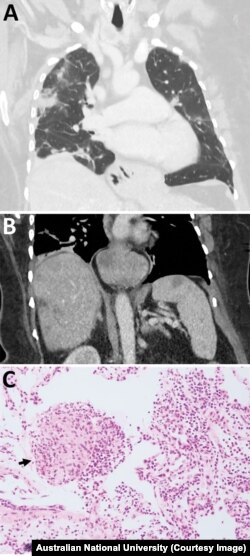

آسٹریلوی مریضہ کے دماغ کا عکس

جنوری 2021 میں انہیں ہسپتال میں داخل کر لیا گیا۔ اور ایک سکین میں ان کے دماغ میں کوئی ابنارمیلٹی دیکھی گئی۔

جون 2022 میں کینبرا ہاسپیٹل میں ان کی بائیوپسی کی گئی اور یوں کیڑے کا علم ہوا۔

محققین کی ٹیم کو خدشہ ہے کہ اس کیڑے کا لاروا یا بہت ابتدائی کیڑے اس خاتون کے جسم کے دیگر حصوں مثلاً پھیپھڑوں اورجگر جیسے اعضاء میں موجود ہو سکتے ہیں۔